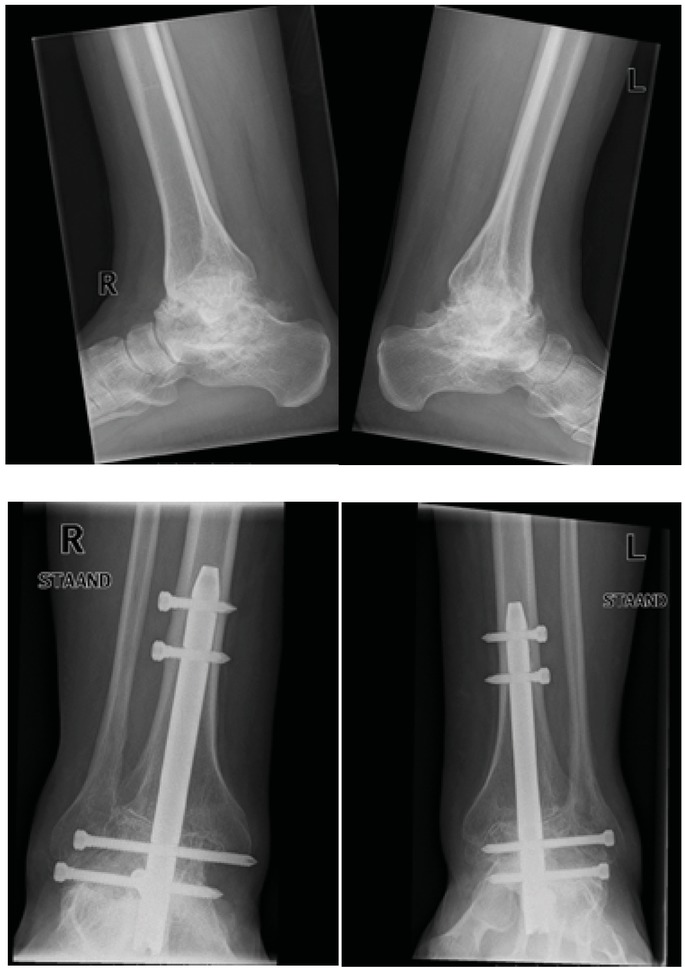

Figure 4

Case 1 X-rays before (2005) and after (2007) bilateral pan arthrodesis by means of an ankle arthrodesis nail in 2006

Case 1 – Bilateral ankle arthrodesis

Post-operative pain assessment scores on the VAS (0–10) was on average 0.3 (range 0–1), indicating minimal pain in all cases. Retrospectively pain improved of all the joints operated on: Case 1: LK 3 and 1 (△= 2) and RK 3 and 1 (△= 3); Case 2: LA 2 and 0 (△=2) RA 2 and 0 (△=2); Case 3: LK 3 and 0 (△=3) and RK 3 and 0 (△=3). The active range of motion of four knees (cases 2 and 3) increased between 5 and 10 degrees, and extension 0 till 20 degrees. As a result of the fixation of the tibiotalar joint, active range of motion decreased in case 1; plantar flexion average 15˚ (range 10– 20˚) and dorsiflexion average 7.5˚ (range 5–10˚).